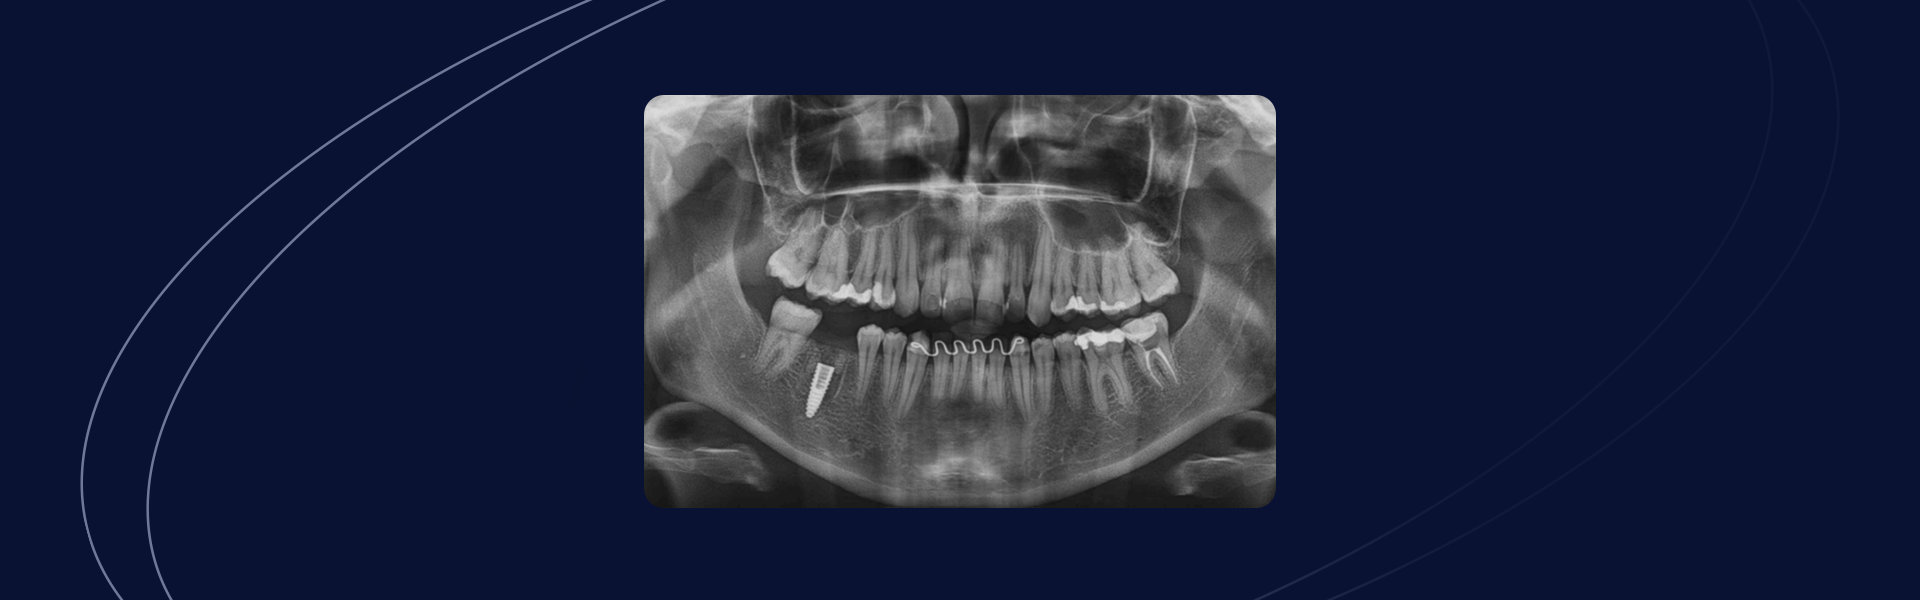

Autores: Diego Bazan e Fábio Lorenzoni Gênero e idade do paciente: Paciente do sexo masculino, 57 anos de idade. Queixa Principal Necessidade de exodontias e implantes dentários Avaliação inicial Após anamnese detalhada o paciente apresentava um bom estado de saúde geral. Durante o exame clínico e radiográfico foi detectado dente 46 com fratura radicular e […]

Preenchimento Alveolar de Elemento Posterior com Fratura Associada à Restauração de Amálgama

Autor: Thiago Roberto Gemeli Amplas restaurações de amálgama comumente estão associadas à fraturas dentais, que por vezes, podem comprometer a permanência desses elementos em função. Quando a substituição de um elemento dentário por um implante se faz necessário e possível, uma série de avaliações locais são realizadas para tornar o resultado mais assertivo e previsível. […]

Exodontia e preservação alveolar com Nanosynt e posterior reabilitação com implantes Vezza

Autores: Diego Bazan e Fabio Lorenzoni Gênero e idade do paciente: Paciente gênero feminino, 56 anos Queixa principal: Dente com grande perda de estrutura coronária e necessidade de reabilitação dentária posterior Avaliação inicial Após exame clínico e radiográfico observamos que o elemento 445 apresentava grande perda de estrutura dentária que inviabilizaria a sua manutenção bem […]